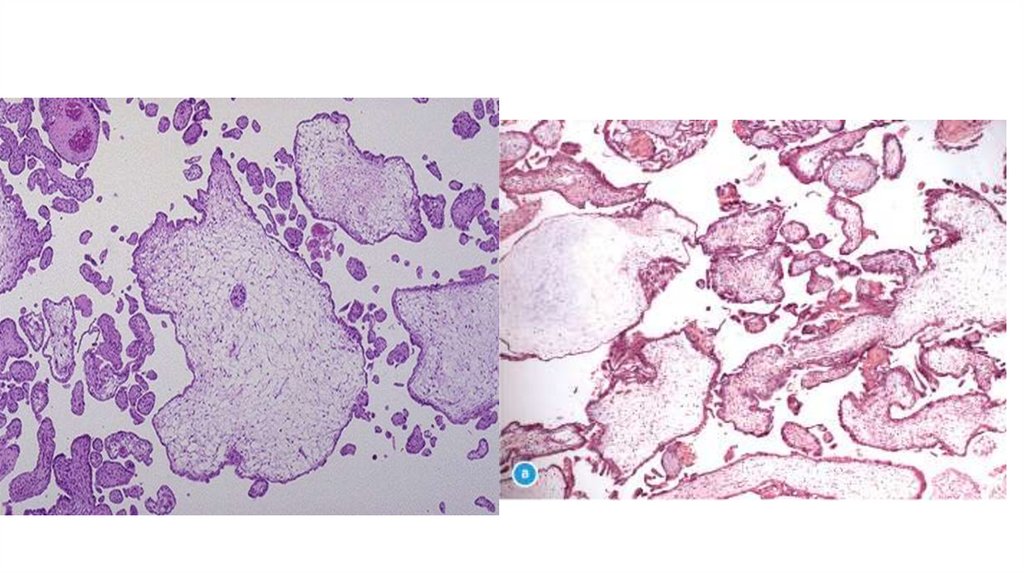

15.

16.

14.

Децидуальная

трансформация

слизистой

оболочки

Ворсины

хориона